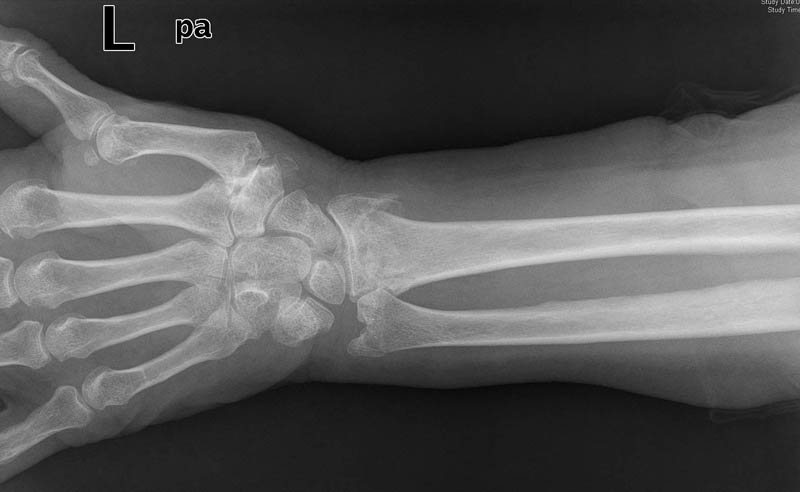

Osteoporosis. Cifosis.

Escoliosis, artrosis, aplastamiento...

Aplastamiento vertebral. Gas. Osteoporosis.

Aplastamiento vertebral. Osteoporosis.